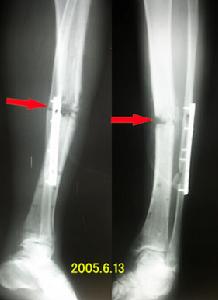

X線檢查平片見脛腓骨上有斷裂,骨皮質不連續並有切跡者,骨密度增高和骨膜增厚硬化基本上在所有病例中都可以出現,骨小梁粗亂、排列不整齊,並可見模糊不完全性骨折線,嚴重病例骨骼變形及周圍軟組織的損傷。

結合臨床及X線表現多可確診,但疲勞性脛腓骨骨折有時需與骨樣骨瘤及青枝骨折、局部骨感染、早期骨腫瘤等鑑別。

疲勞骨折與以上各種骨疾病雖有相同的局部骨膜反應、骨皮質增厚硬化等表現,但它仍有自身的特點,只要掌握X線特點及臨床病史,即可對疲勞性骨折作出正確的診斷。